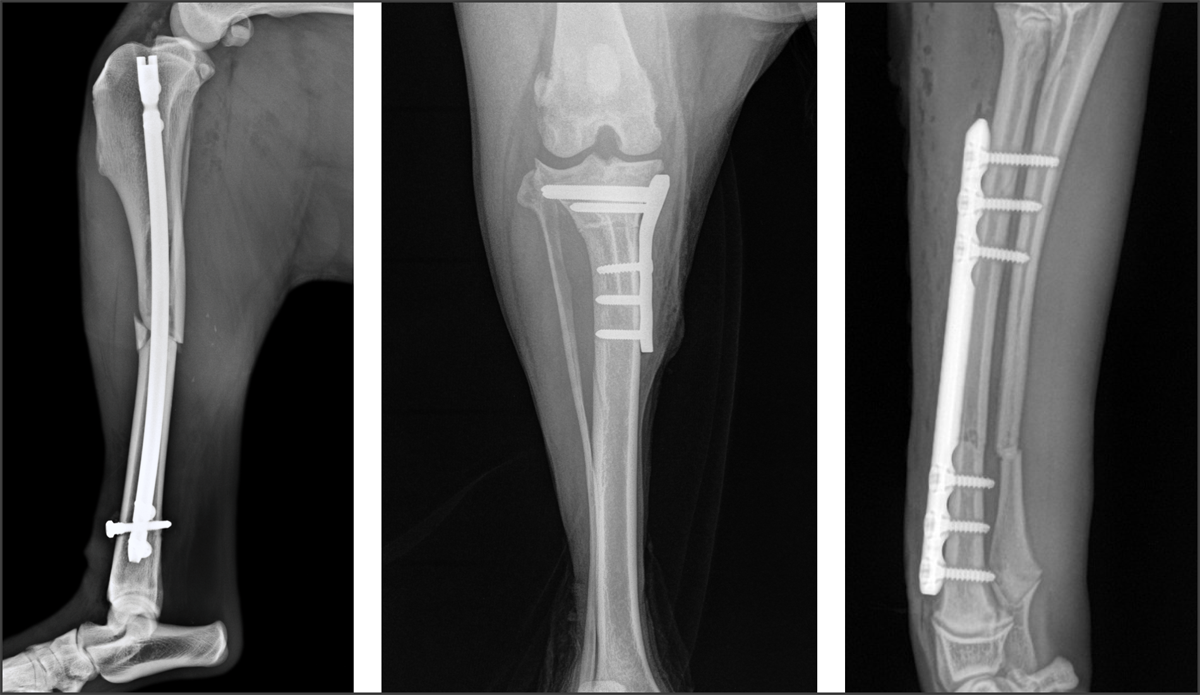

By offering the Surg’X Interlocking Nail System, the Securos locking trauma and joint management plating systems, as well as a cannulated bone screw system, we are producing best-in-class orthopedic solutions tailored to the way you deliver veterinary care.

Securos Orthopedics X-Ray